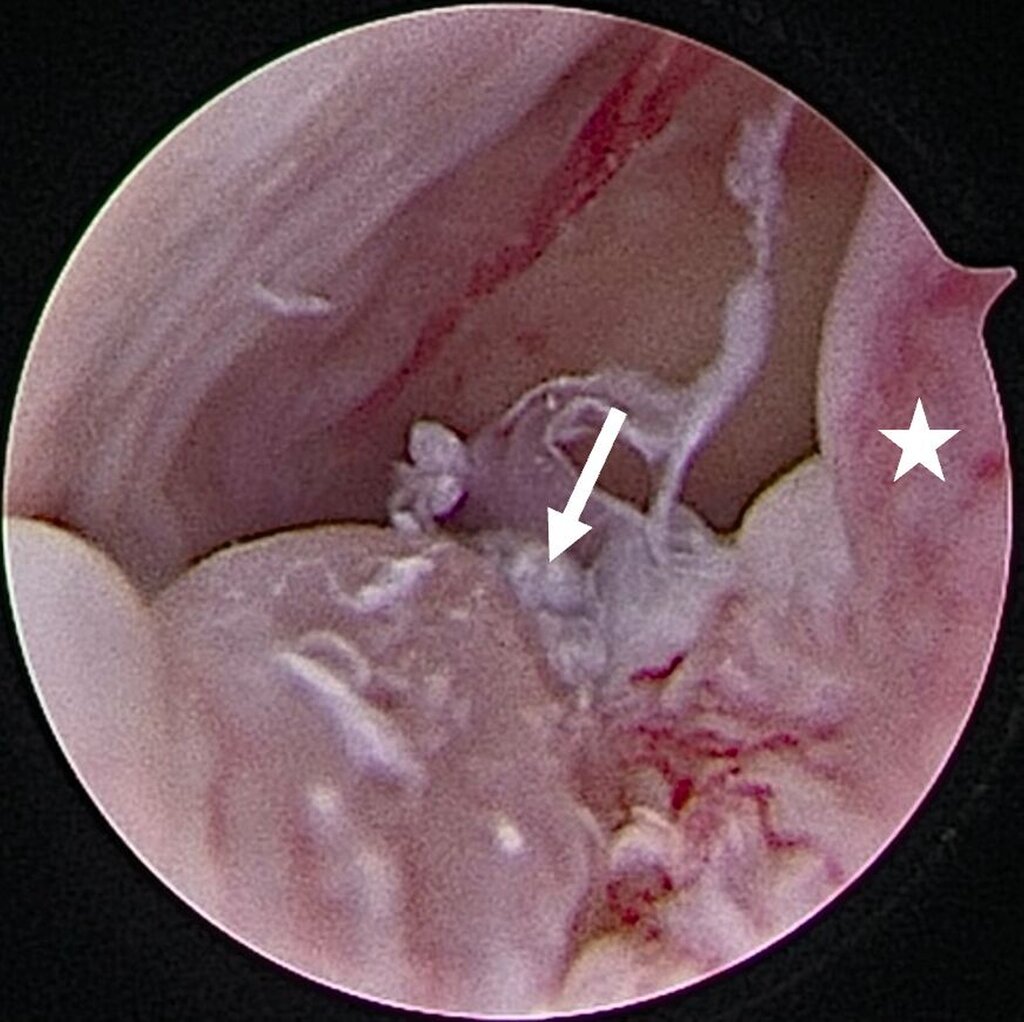

Eine Entzündung im Bereich der Gelenkkapsel (Synovitis) stellt eine häufige Ursache für arthrogen bedingte Beschwerden dar [Mercuri et al., 2025]. Neben der Darstellung des Gelenks und der Behandlung von Pathologien beruht ein positiver Effekt der Arthroskopie auf der Lavage des Gelenks. Dadurch können zum Beispiel proinflammatorische Mediatoren entfernt und intraartikuläre Adhäsionen gelöst werden [Soni, 2019]. Abbildung 2 zeigt die intraoperativen Befunde von zwei Patienten. Es wird jeweils der Übergang zwischen dem hinteren Aufhängungsband und der pars posterior des Discus articularis dargestellt.

Ein Patient stellte sich in unserer Klinik mit einer seit zwei Wochen bestehenden Okklusionsstörung vor. Klinisch zeigte sich bei habituellem Mundschluss eine Protrusionsstellung des Unterkiefers. Darüber hinaus berichtete der Patient über Schmerzen im linken Kiefergelenk, insbesondere bei Mobilisation nach dorsal. Durch die zeitnah durchgeführte MRT-Untersuchung wurde eine synoviale Chondromatose des linken Kiefergelenks diagnostiziert. Die beschriebene Symptomatik wurde am ehesten von einem circa 8 mm großen freien Gelenkkörper im dorsalen Bereich des Gelenks verursacht, der ein Zurückgleiten des Diskus articularis (beziehungsweise des Kondylus) verhinderte (Abbildung 7).

Im Rahmen einer Level-II-Arthroskopie (Abbildung 8) in Vollnarkose konnte der Gelenkkörper nach Zerkleinerung durch Coblation über einen Arbeitskanal vollständig entfernt werden. Die histologische Aufarbeitung ergab hyalinen Knorpel mit (sklerosiertem) Bindegewebe. Der Eingriff verlief komplikationslos; postoperativ zeigte sich unmittelbar eine regelrechte Okklusion. Die Schmerzen waren am ersten postoperativen Tag bereits vollständig regredient.